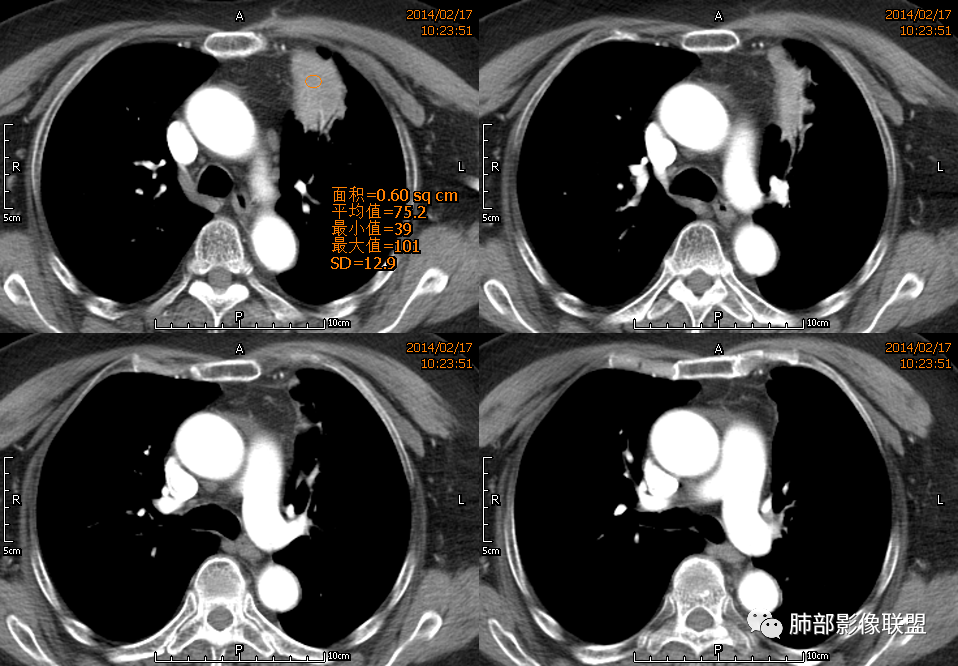

宽基底,附近胸膜增厚,边缘平直

支气管通畅

血管走形自然

坏死灶边界清附近卫星灶

意见:支持炎性。治疗后复查以排除恶性病变隐藏其中

1、坏死区环形强化,指向慢性脓肿。

2、坏死区有血管,基本排除结核。

3、这个卫星灶,更进一步定了大方向,炎性。

※综上所述,看到这四幅图,基本能够准确诊断炎性※

2.左肺上叶前段胸膜下块状影,不规则呈“逗点样”延向肺门区,边界清楚,未见分叶、毛刺及张力,表面不规则棘突,状如“火焰”或“日冕”。相邻胸膜增厚,未见栽赃、卫星病灶。

3.病灶密度不均,中央坏死液化并见气泡影,支气管及血管贴边进入,较均匀环形强化(显示多层结构),未见明确壁结节。

3.病灶易坏死液化,环形强化,支气管及血管贴边进入,“火焰”样边缘轮廓,更符合炎性块影的特点。